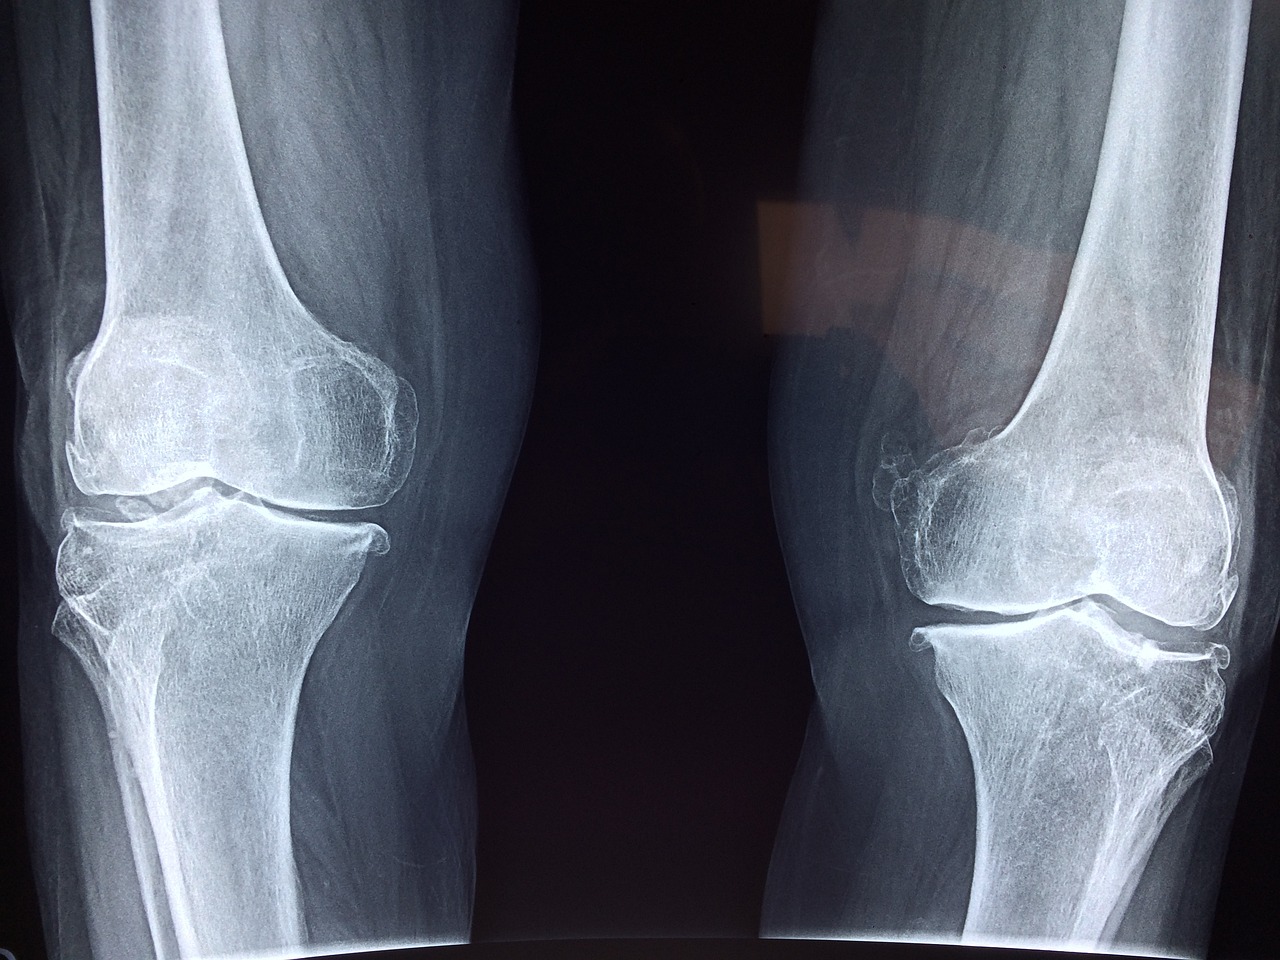

마치며.. 무릎 통증이 자주 발생한다면 병원을 방문하여 X-ray 또는 MRI 검사를 통해 정확한 원인을 진단받고, 적절한 운동 처방이나 물리치료를 병행하는 것이 바람직합니다. 일상의 작은 습관 변화가 중장년층 무릎 건강을 지키는 큰 차이를 만들어냅니다.